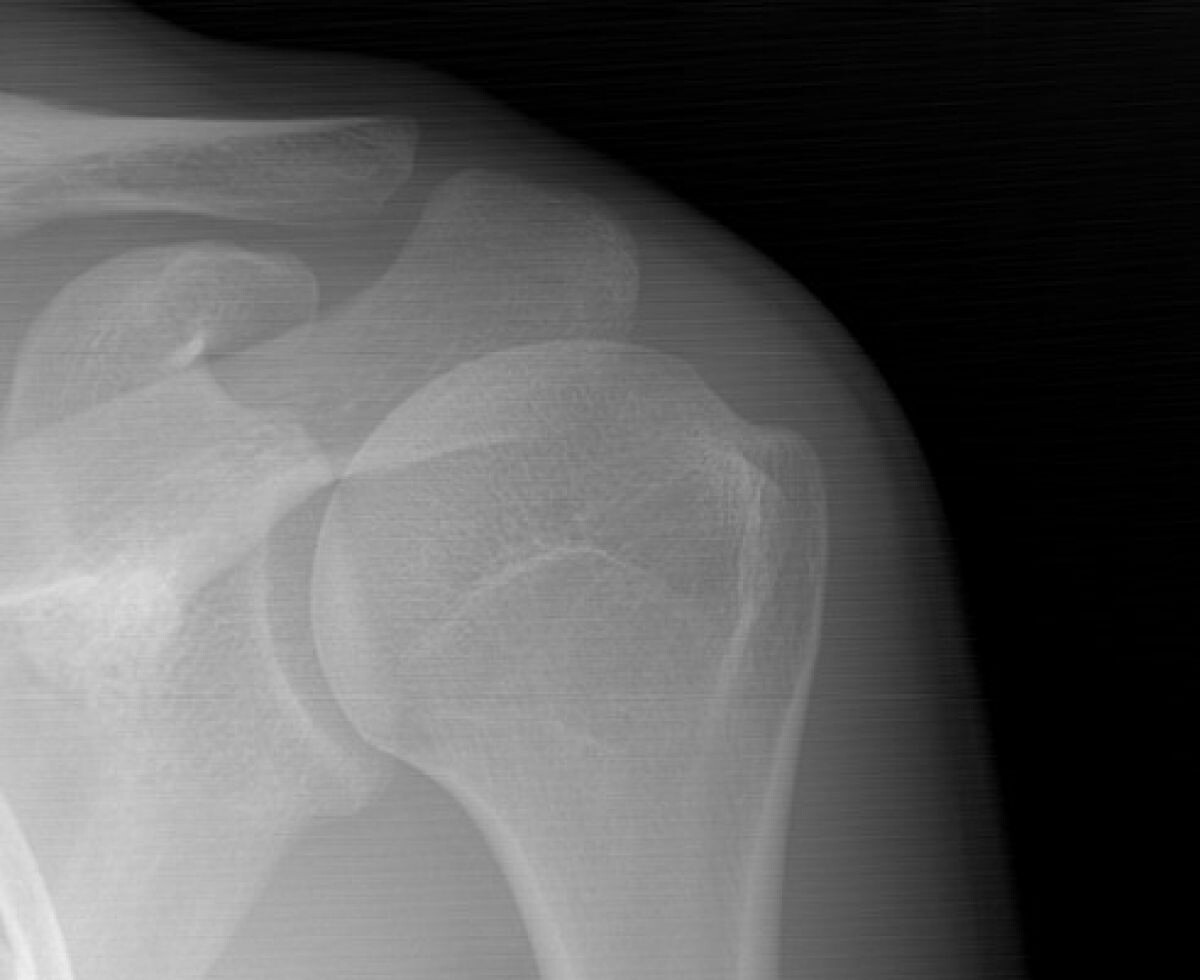

С 10 по 16 ноября Амбулаторно-травматологический центр Больницы скорой медицинской помощи в Рязани принял 549 пациентов с травмами опорно-двигательного аппарата. Наибольшее количество обращений — 195 — связано с ушибами, 137 — с переломами, 118 — с растяжениями связок, 35 — с ранами. Центру, работающему в режиме 7/24 (без выходных и круглосуточно), ежедневно приходится принимать сотни жителей, нуждающихся в неотложной и специализированной помощи.

Наибольшее количество обращений — 195 — связано с ушибами, 137 — с переломами, 118 — с растяжениями связок, 35 — с ранами.